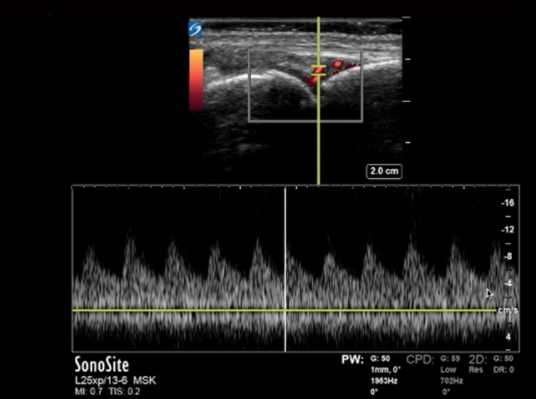

Hand Joint Synovitis with Doppler Image